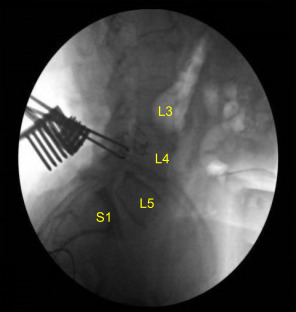

The C-arm unit, which was draped sterilely, was brought into the field and used to confirm the level. Neuronavigation array was affixed to the right superior posterior iliac crest with two Schanz pins after infiltrating with local anesthesia and making #15 blade stab incisions.

CT scan was then obtained (shown above) which showed correct positioning of all the hardware. Neuromonitoring signals were stable. The wound was irrigated copiously. Bilateral transverse processes were decorticated for posterolateral arthrodesis from L4 to S1.